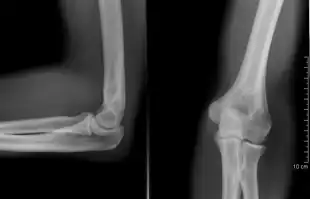

The elbow is the region between the upper arm and the forearm that surrounds the elbow joint.[1] The elbow includes prominent landmarks such as the olecranon, the cubital fossa (also called the chelidon, or the elbow pit), and the lateral and the medial epicondyles of the humerus. The elbow joint is a hinge joint between the arm and the forearm;[2] more specifically between the humerus in the upper arm and the radius and ulna in the forearm which allows the forearm and hand to be moved towards and away from the body.[3][4] The term elbow is specifically used for humans and other primates, and in other vertebrates forelimb plus joint is used.[1]

When in anatomical position there are four main bony landmarks of the elbow. At the lower part of the humerus are the medial and lateral epicondyles, on the side closest to the body (medial) and on the side away from the body (lateral) surfaces. The third landmark is the olecranon found at the head of the ulna. These lie on a horizontal line called the Hueter line. When the elbow is flexed, they form a triangle called the Hueter triangle, which resembles an equilateral triangle.[5]

At the surface of the humerus where it faces the joint is the trochlea. In most people, the groove running across the trochlea is vertical on the anterior side but it spirals off on the posterior side. This results in the forearm being aligned to the upper arm during flexion, but forming an angle to the upper arm during extension — an angle known as the carrying angle.[6]